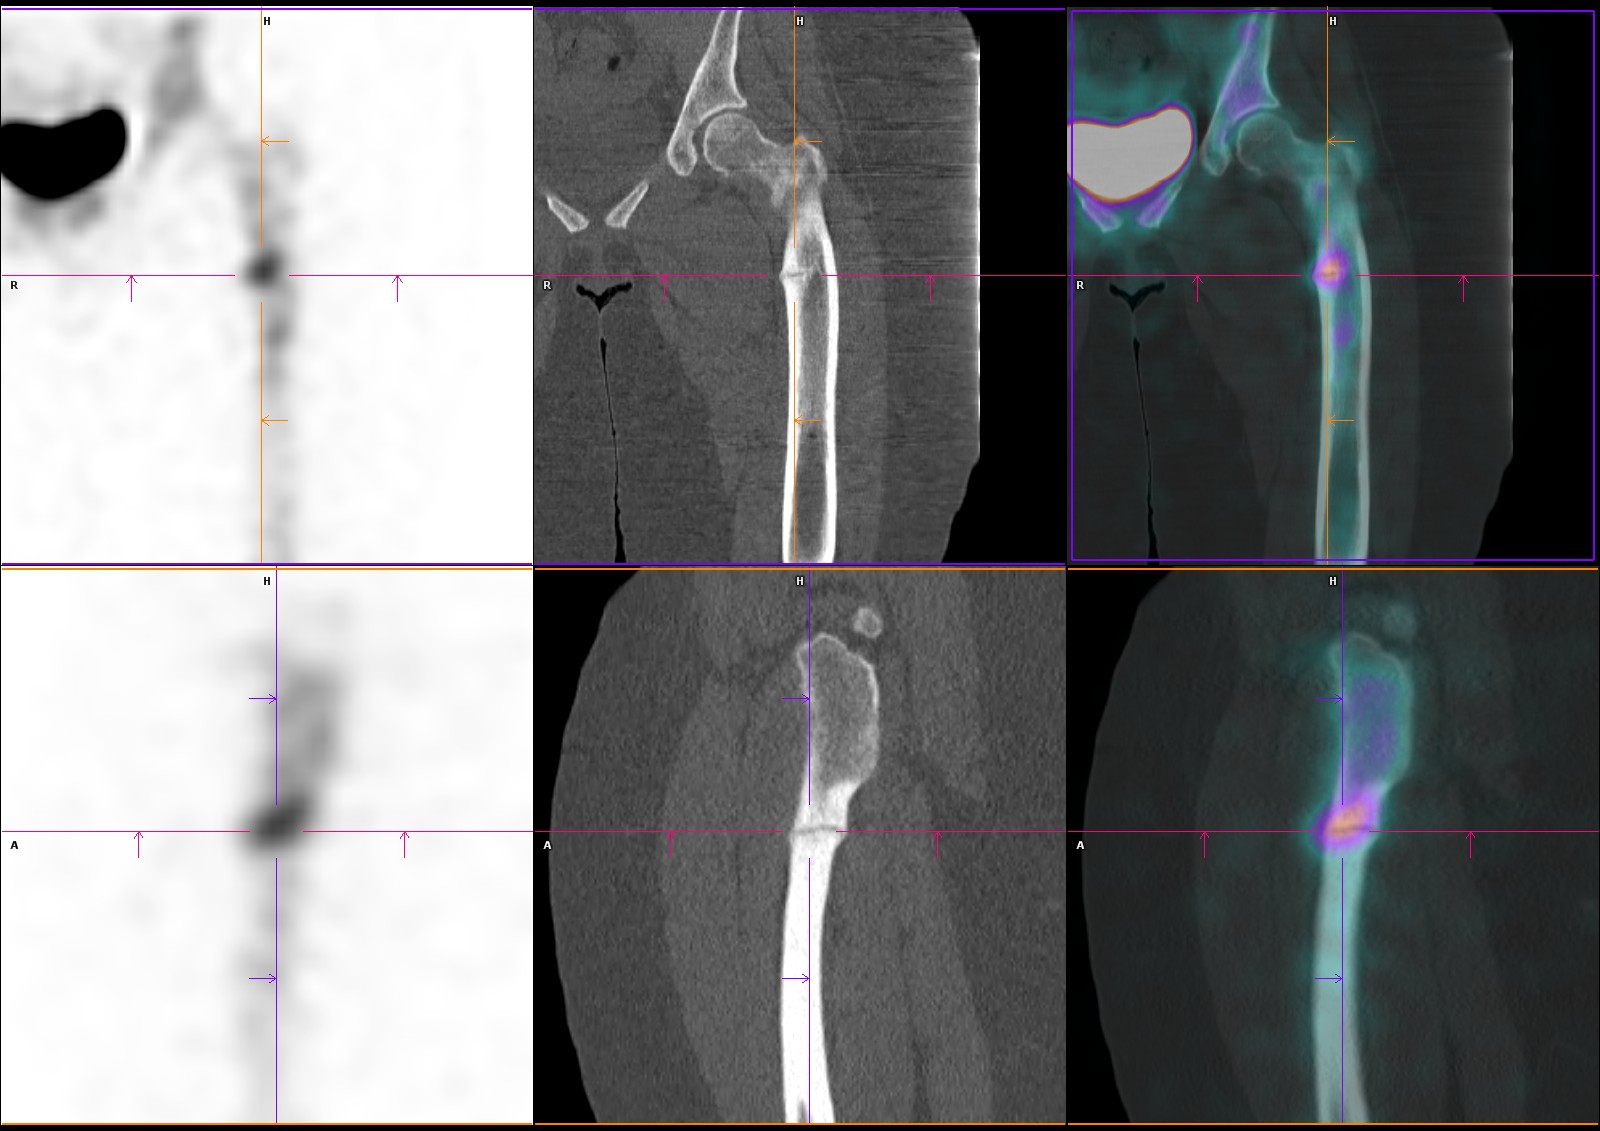

Hyperfixations en regard d’encoches corticales radiotransparentes perpendiculaires à l’axe de l’os, des métaphyses fémorales bilatérales et de la métaphyse tibiale droite (en zones portantes).

Aspect typique de stries de Looser-Milkman, spécifiques de l’ostéomalacie.